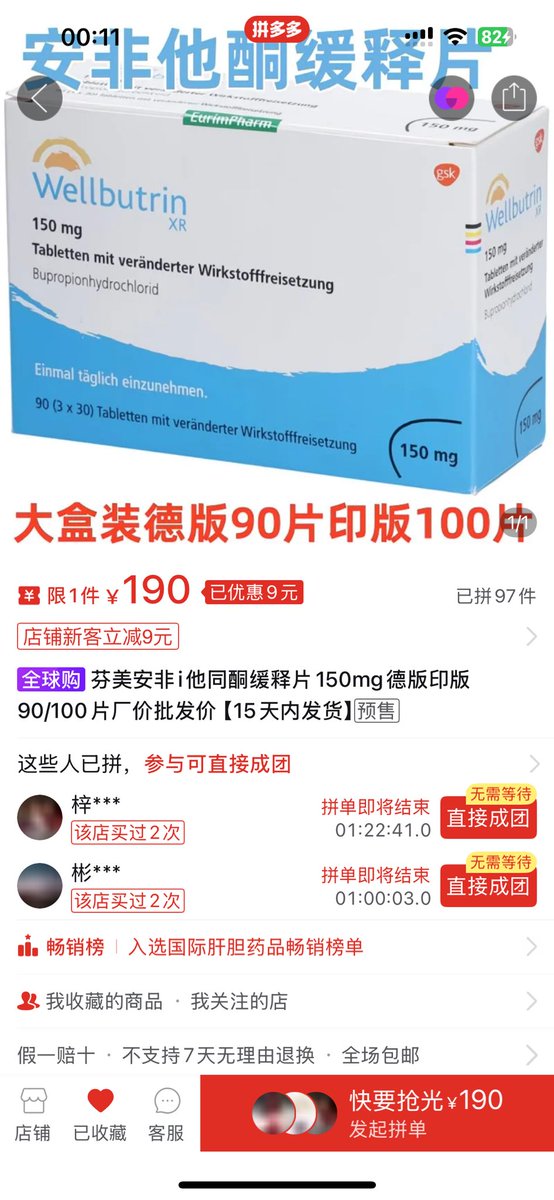

首先,从定义上讲,“反解离(anti-dissociative)”并不是一个标准的医学术语或者广泛认同的药理学分类。在正规资料,比如医学文献、维基百科、精神药理学教科书中,目前并没有“反解离药物”这个正式概念。

看上去像是为了描述某类特定效应而创造的术语(可能是nmda受体活性增强),用来对抗因NMDA受体拮抗剂(比如氯胺酮、DXM、PCP等)引发的解离体验(dissociation)。

那么更常见的是将其归入认知增强剂(cognitive enhancers),特别是改善认知连接性(connectivity)和现实感知(reality testing)的类型。

但其实在药理学上,单纯用“受体激动剂”来逆转“受体拮抗剂”的效应,有时会导致过度激活。

对于NMDA受体而言,过强的NMDA活化本身就与兴奋性毒性(excitotoxicity)和精神病样症状(psychotomimetic effects)有关,比如谷氨酸风暴可以引发严重的焦虑、妄想、乃至癫痫。

也就是说,简单地“激动-解除拮抗”在中枢神经系统是很危险的做法,尤其是对于易感个体(如有精神分裂素质的人)。

科学的处理方式一般是通过更细致的调节,比如微调NMDA/AMPA平衡、调节其他辅助途径(如GABA、5-HT、mGluR受体),而不是简单粗暴地用“NMDA增强剂”去顶回去。

而临床处理药物中毒中,其实医生更常用的做法是保守、支持性的治疗,比如补液,促进代谢,必要时镇静,以及监测生命体征防治并发症。

药物拮抗与受体激动之间,往往牵扯到的是复杂的适应性变化(receptor upregulation/downregulation),

不是简单的“给多一点刺激就能抵消”的关系